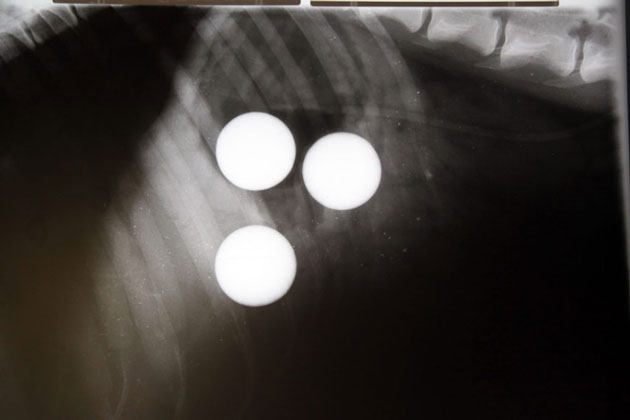

سگی که سه توپ گلف را قورت داده بود(+عکس)

عصر ایران - این سگ نژاد دوبرمن در انگلیس وقتی 3 توپ گلف را می بلعد حالش بد می شود و صاحبش متوجه می شود که او روز به روز لاغرتر و نحیف تر می شود .

نتایج آزمایش ها و سونوگرافی نشان می دهد او سه توپ گلف را بلعیده است . پس از خارج کردن سه توپ از بدن این سگ حال او بهبود می یابد.